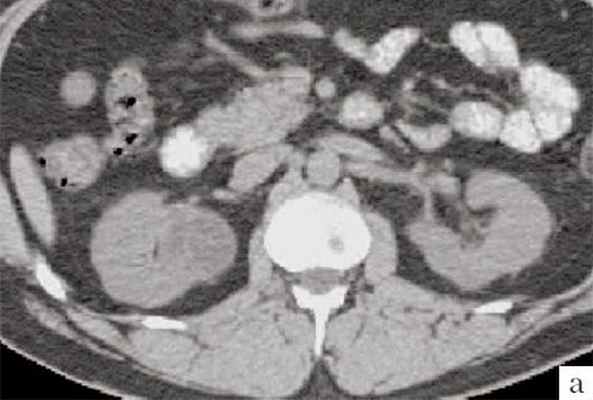

Достоверность комьютерной томографии (КТ) в диагностике мультилокулярной кистозной нефромы, по данным разных авторов, составляет от 95 до 98%. При КТ определяется негомогенное многокамерное образование округлой или неправильно-округлой формы, возможно с капсулой, плотность образования неоднородная, пониженная относительно паренхимы, в полости образования определяется большое количество перегородок (рис. 3). Если при КТ с контрастированием происходит накопление контрастного вещества, это может быть признаком предполагаемой малигнизации [11, 13, 19].

а) До внутривенного контрастирования определяется негомогенное образование неправильной округлой формы с капсулой и едва заметными перегородками, плотность ниже, чем плотность паренхимы почки.

б) После контрастирования отчетливо выявляются плотная стенка и множество перегородок.

Компьютерная томография. В нижнем полюсе правой почки определяется неоднородное образование, с четкими неровными контурами, округлой формы, в диаметре до 30 мм, неоднородно пониженной плотности от +15 до +18 HU по шкале Хаунсвильда. После внутривенного контрастирования образование не изменят свою форму, размеры и плотность. В полости образования выявляются множественные перегородки, накапливающие контрастное вещество, единичный кальцинат.

Заключение: Сложное кистозное образование нижнего полюса правой почки, больше данных о мультилокулярной кистозной нефроме (рис. 5).

а) До внутривенного контрастирования определяется негомогенное образование округлой формы, с единичным кальцинатом, плотность ниже, чем плотность паренхимы почки.

б) После контрастирования (паренхиматозная фаза) отчетливо выявляются плотная стенка и множество перегородок.